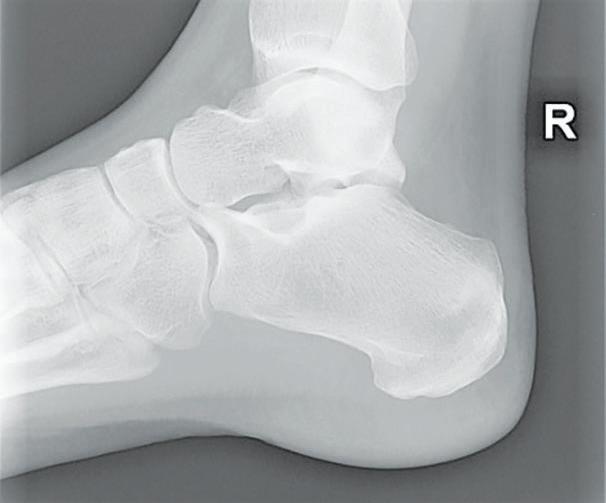

To my surprise, I not only had one, but three stress fractures on my tibia and ankle.

Stress fractures are tiny cracks in a bone. They’re caused by repetitive force, often from overuse — such as repeatedly jumping up and down or running long distances. Stress fractures can also develop from normal use of a bone that’s weakened by a condition such as osteoporosis.

Stress fractures are most common in the weight-bearing bones of the lower leg and foot. Track and field athletes and military recruits who carry heavy packs over long distances are at highest risk, but anyone can sustain a stress fracture. If you start a new exercise program, for example, you might develop stress fractures if you do too much too soon.

Foot problems People who have flat feet or high, rigid arches are more likely to develop stress fractures. Worn footwear contributes to the problem.